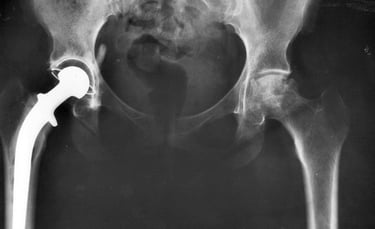

Hip Joint Infection

A hip infection happens when germs get into the bone or joint and reproduce. Viruses, bacteria, fungi and parasites can all cause infections. Our skin normally has bacteria on it. It is these germs that most often cause infections in the bones and joints.